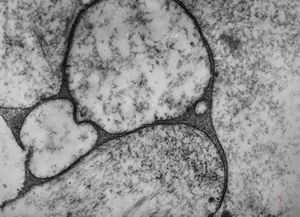

M,33y. | blood - hairy cell leukemia- ribosome-lamella complexin tricholeukocyte